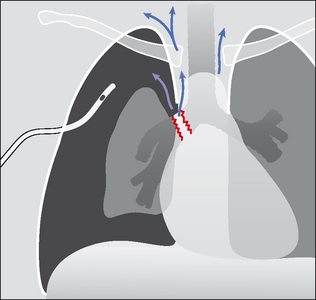

QUESTION 5—IS THERE A TRACHEO-BRONCHIAL RUPTURE?

These injuries result from very violent trauma—usually a deceleration force applied to the anterior chest wall. An injury to the great vessels or an intracranial injury are recognised associations of tracheal or bronchial rupture.

image CXR features4,12 suggesting a tear of a main airway (transection or rupture):

image Pneumomediastinum.

image Lobar collapse. Either because the torn bronchus results in deflation, or because blood occludes the bronchial lumen. Whatever the cause, a lobar collapse may not occur for a few days.

image A pneumothorax that does not resolve following intercostal tube drainage12.

image Pitfall: the significance of any one of these three important CXR features may not be appreciated…because their appearance can be delayed.

image Consequences of a tear/rupture:

image High mortality.

image Broncho-pleural fistula.

image Eventual bronchostenosis (scarring with narrowing).

Figure 32.13 Violent trauma. Rupture of a main bronchus. This can cause a pneumomediastinum (arrows), and/or a pneumothorax that fails to absorb following insertion of an intercostal drain, and/or persistent lung or lobar collapse (i.e. persistent lung deflation).